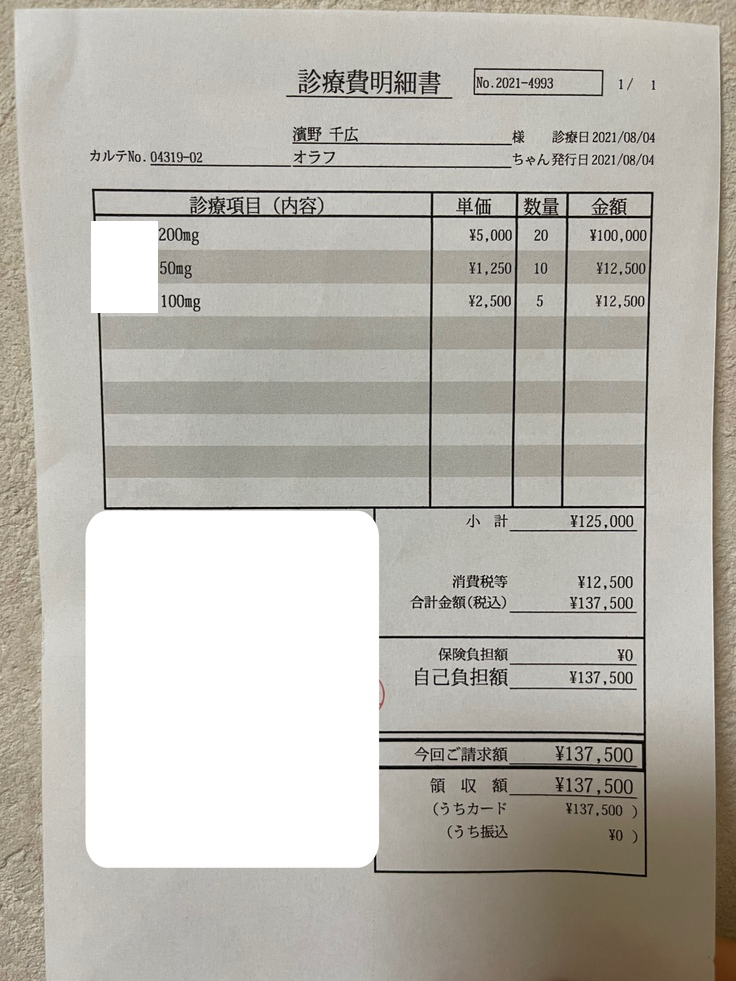

8月4日

7月29日に少し新薬を貰っていたので、この日は追加で新薬を貰いました。

検査費と薬代です。

オラフの体重は3.0kgで1日450mg(計3錠)投与となります。

200mg(5,500円税込/錠)×2

100mg(2,750円税込/錠)

50mg(1,375円税込/錠)×1

3.4kgまでは1日¥12,375となります。